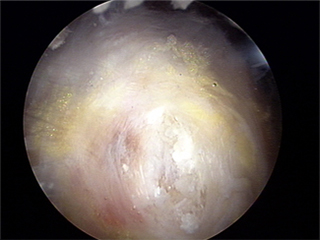

관절경 수술 후